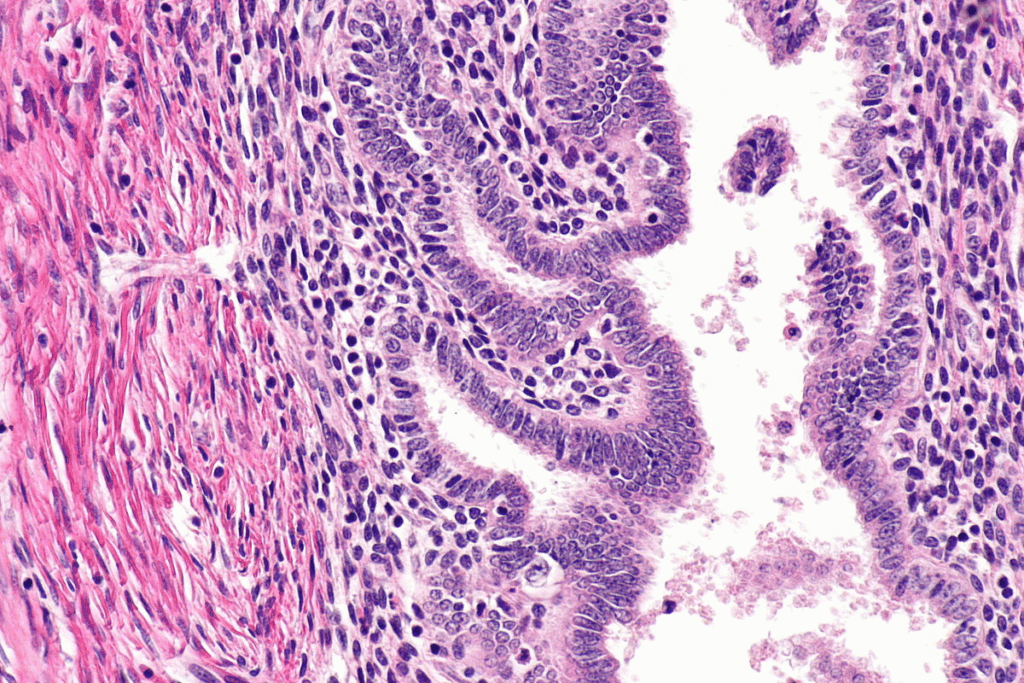

Uterine fibroids, or leiomyomas, are non-cancerous tumors in the uterus. They can cause symptoms that might need surgery. We’ll look at what these growths are, symptoms that might need surgery, and how doctors decide on surgery.

What Are Uterine Fibroids?

Uterine fibroids are non-cancerous growths in or around the uterus. They can be different sizes, numbers, and locations. These growths are common among women of reproductive age. The exact cause is unknown, but genetics, hormones, and environment play a role.